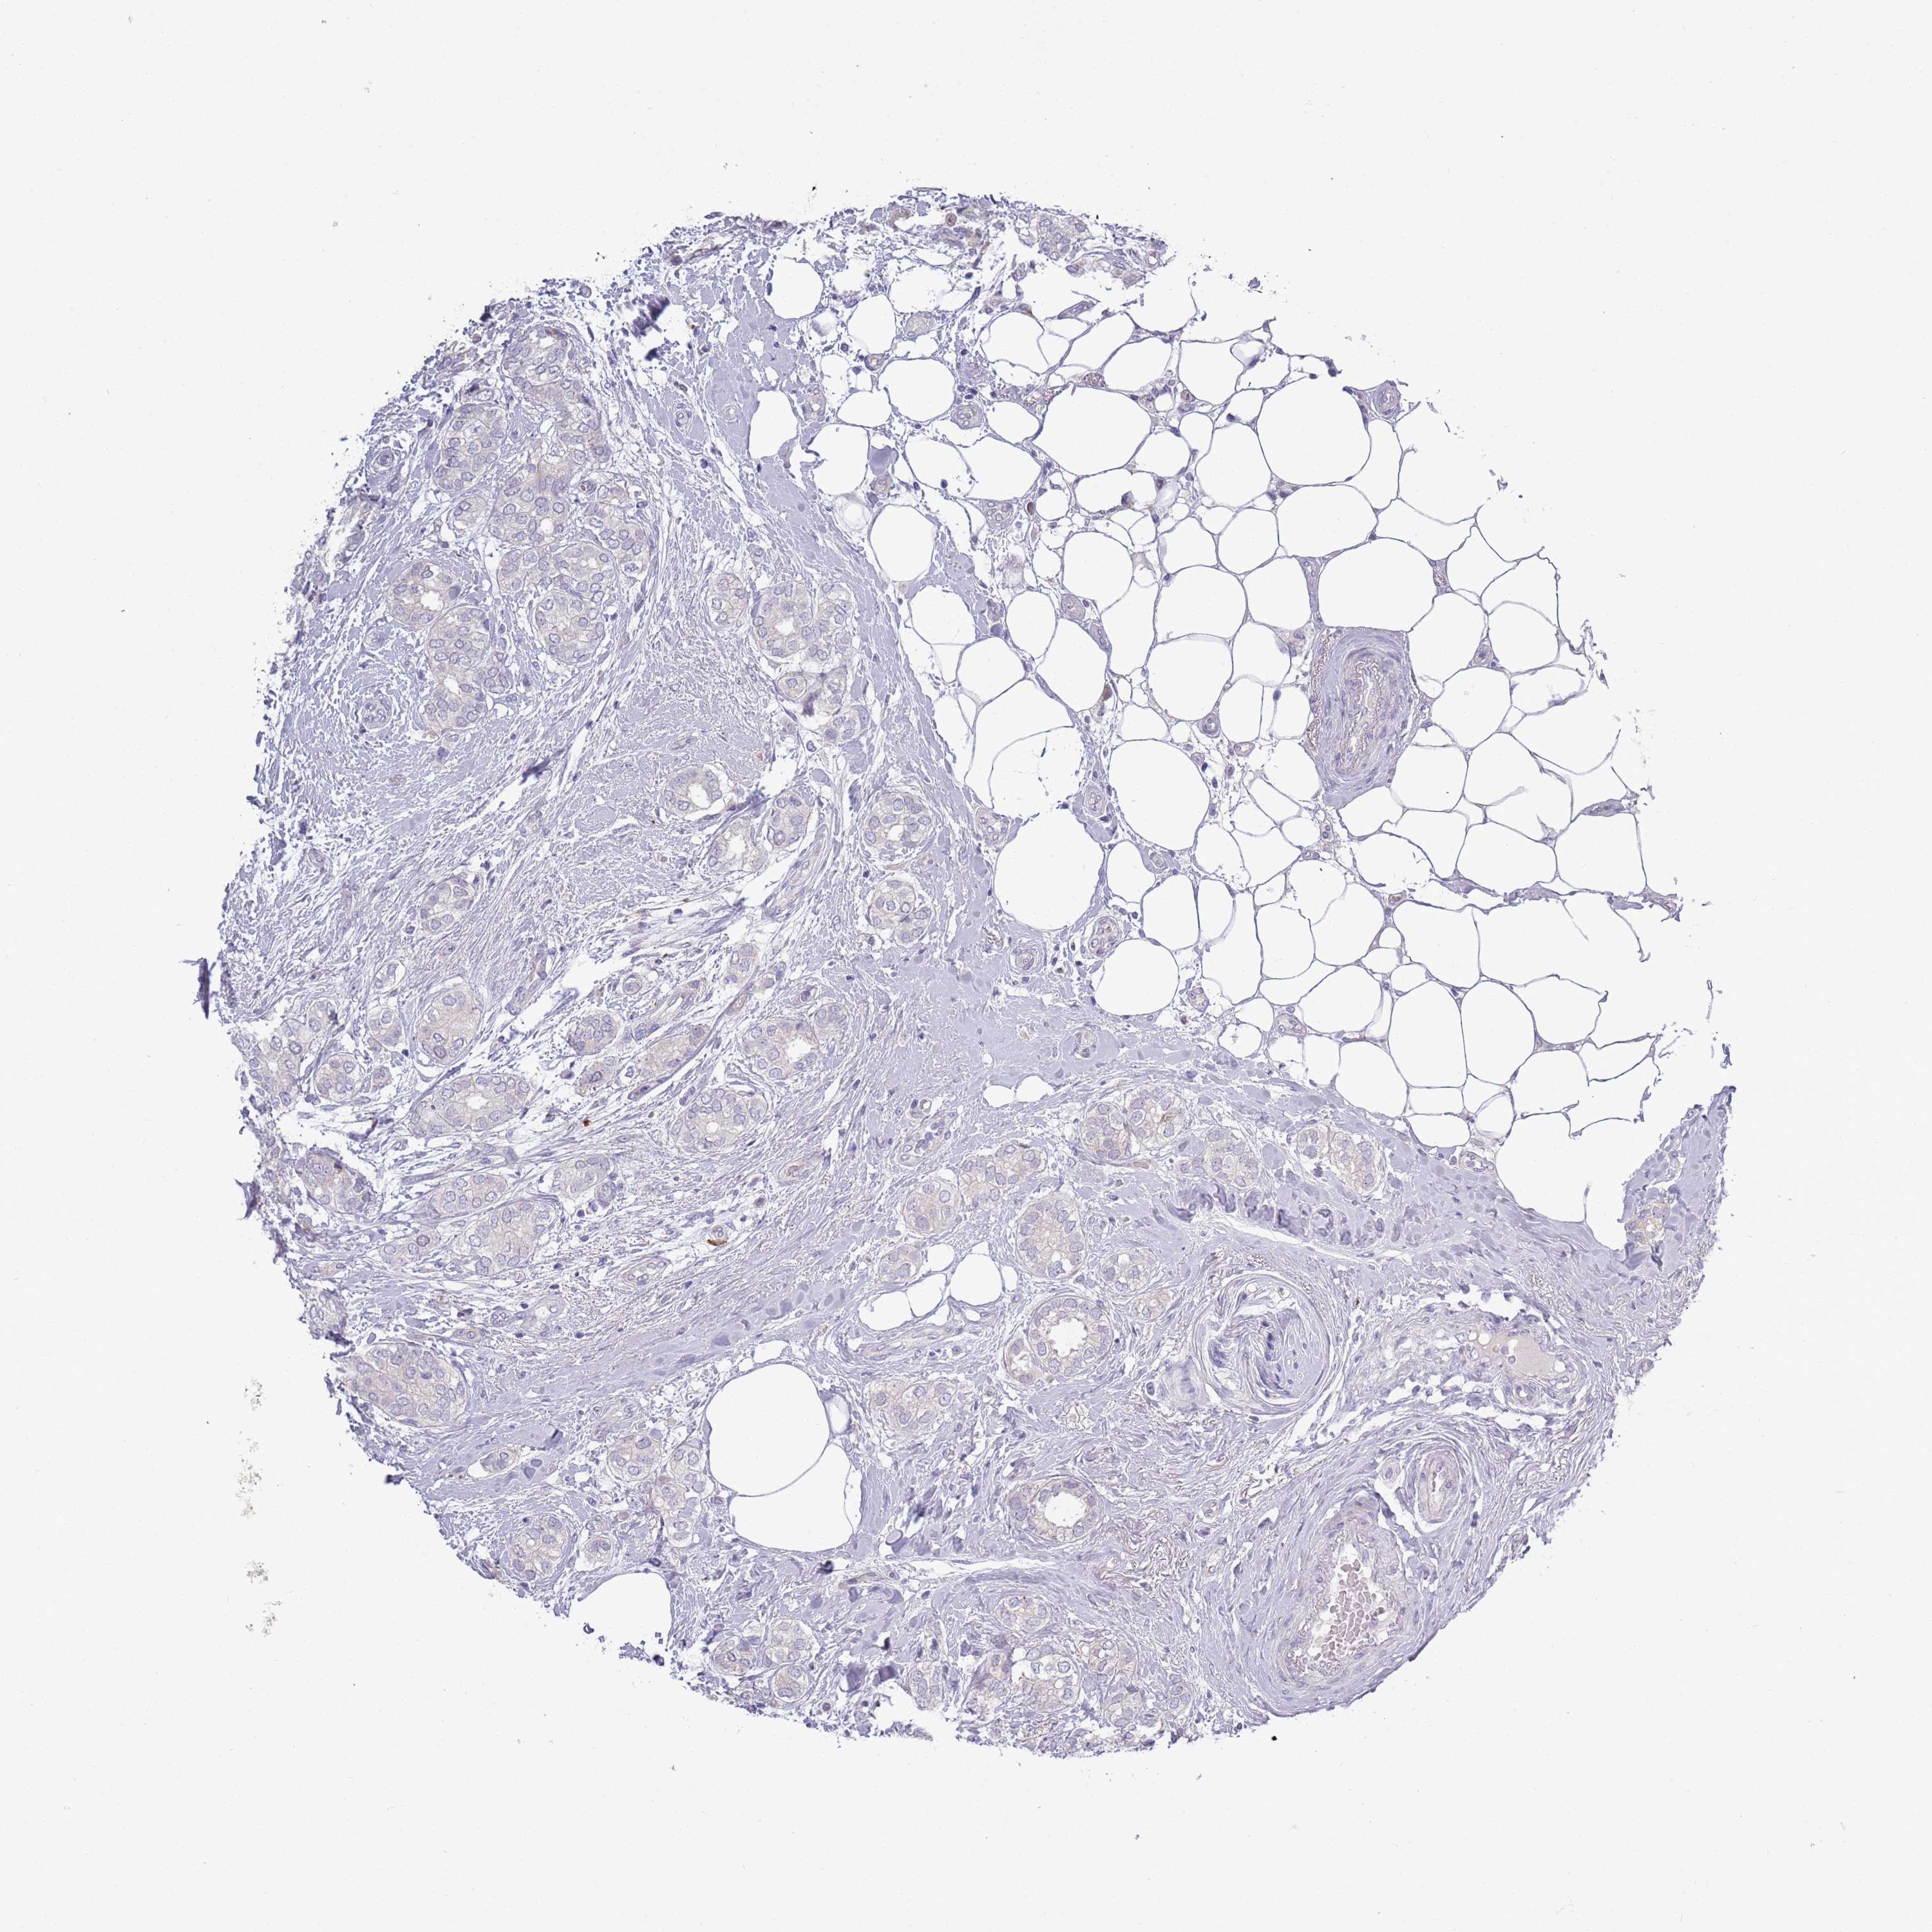

CANCER BREAST CANCER Show tissue menu

BRCA TCGA BRCA VALIDATION PROTEIN EXPRESSION